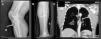

We present the case of a 48-year-old man who had no significant familial or personal history, and was being treated with nonsteroidal anti-inflammatory drugs (NSAID) to relieve widespread pain that had begun months earlier. He was admitted by the orthopedic department due to pain and to the sudden onset of functional incapacity in both knees. The diagnosis was rupture of the patellar tendons, and he was scheduled for surgical reinsertion. A radiograph of lower limbs showed nonossifying fibromas in right anterior tibial tuberosity and in the middle third of left tibia (Fig. 1). In the preoperative study, he underwent a chest radiograph, which revealed a nodular structure in left hemithorax. The study was completed with chest computed tomography, which disclosed the presence of a lytic lesion growing toward the pleura. The lesion, in the left 5th rib, had a diameter of 5cm, and suggested a possible bone metastasis (Fig. 1), although no other changes were observed.

The patient underwent surgery in both knees, with suturing and osteosynthesis involving the patellar tendon, and a specimen was taken of the fibroma in right anterior tibial tuberosity. The pathological report described a giant cell tumor suggestive of a brown tumor associated with hyperparathyroidism, but it was not possible to rule out a giant cell reparative granuloma. After controlling hypercalcemia with intravenous bisphosphonates, neck surgery was performed and a left inferior parathyroid adenoma was resected. As a result, a normal serum calcium level was achieved and there was a partial improvement in renal function. After a year and a half of follow-up, the bone lesions in tibiae and rib have become smaller, although they have not disappeared.